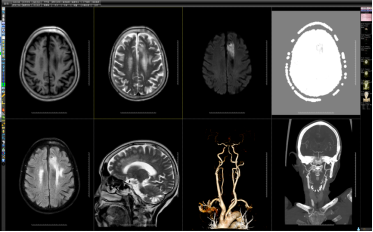

图④

图⑤

图④图⑤为同一卒中患者进行的一站式服务,分别为颅脑灌注成像、头颈CTA、MRI常规扫描及DWI功能成像。